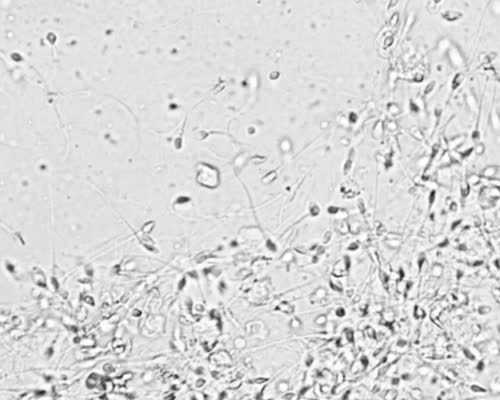

这就是3个医院的广州试管南昌代孕婴儿南昌代孕价格详细目录,每个项目的收费都包括在里面广州哪里试管婴广州医院南昌代孕专家如果DNA碎片率大于25%,即使精子活力、形态正常,也可能由于基因缺失导致南昌代孕女性南昌代孕后出现流产的现象,甚至导致不孕现象(特别蓝瘦、真的很香菇)取卵后,喝水喝汤尽快排尿,排完尿再离开医院。